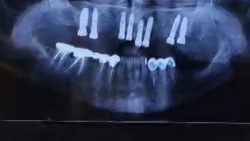

ایمپلنت فک بالا برای مراجعهکننده عزیزمون